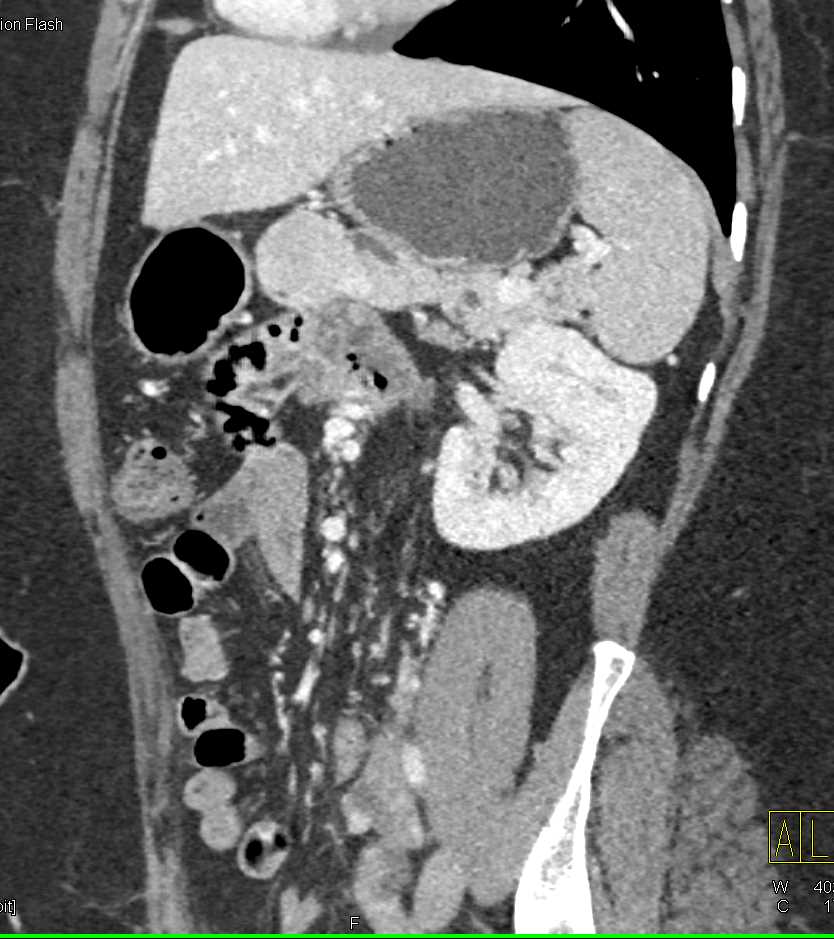

Neuroendocrine Tumor Body of Pancreas